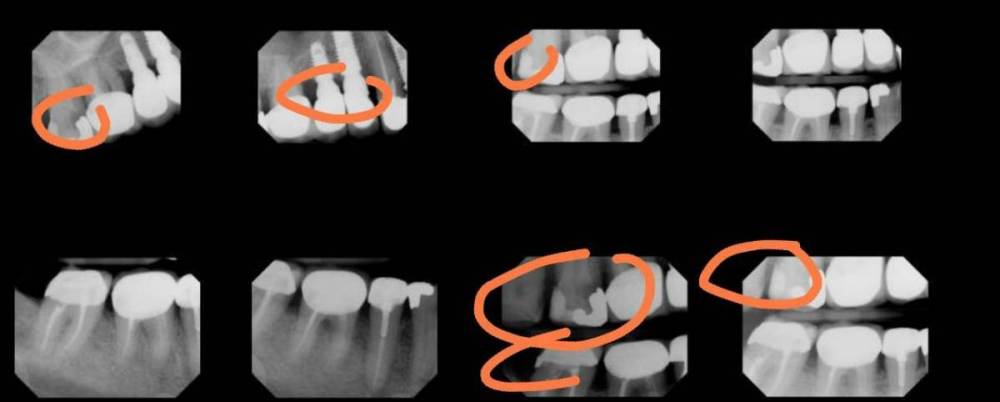

IvanK Опубликовано 14 января, 2023 Поделиться Опубликовано 14 января, 2023 Здравствуйте, для проведения диагностических манипуляций нужно минимум ОПТГ (панорамный снимок). На данных прицельных снимках мы видим кусочки пазла То, что бросилось в глаза при беглом осмотре Ссылка на комментарий

adent Опубликовано 14 января, 2023 Автор Поделиться Опубликовано 14 января, 2023 IvanK спасибо! Для меня это открытие понятие ОПТГ! Попытаюсь найти возможность и сделать такой снимок. Боюсь оказаться навязчивым но не затруднит вас сказать мне номера зубов обведенных наснимке. Иначе я не понимаю, Ну может быть будет ответите в таком виде (понятном для меня): Верхний ряд снимков считаем слева направо 1й снимок –зуб # 2й снимок –зуб # , зуб # 3й снимок-зуб # Нижний ряд снимков считаем также слева направо 3й снимок-зуб # 4й снимок-зуб # Ссылка на комментарий